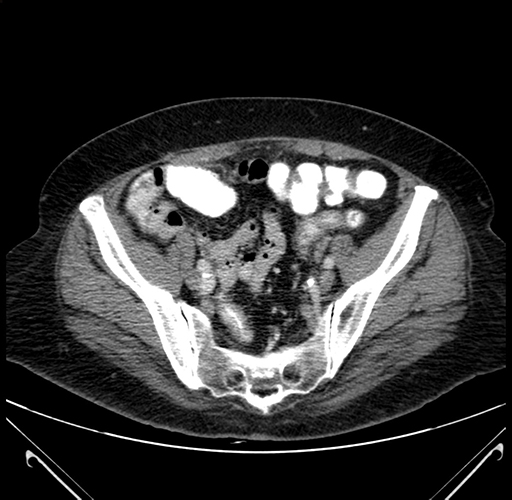

Pre-Chemo: Axial Venous

Axial Venous